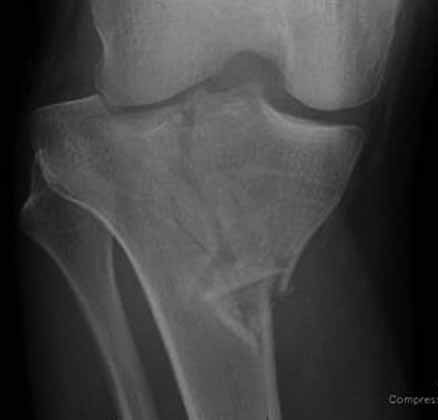

Здравствуйте уважаемые коллеги!Сегодня обратился больной 35л. Травму получил 3 мес.назад, упал в яму, лечился в отдаленном районе гипсовой повязкой, 1 месяц назад гипс сняли , и больной начал ходить с нагрузкой, постепенно появилась деформация коленного сустава, неустойчивость и боли. Локально: деформация коленного сустава, голень смещена кзади- типа подвывиха, разгибание 170гр. Сгибание 150гр.симптомов повреждение коллатеральных и крестообразных связок определить не удается из-за боли и контрактуры. Первичных снимков пока нет, обещали принести, имеется снимки через 2 месяца после травмы без гипса, недельной давности снимки в прямой проекции и К Т. Похоже, что импрессия переднемедиальной части внутреннего мыщелка б/берцовой кости, отрыв межмыщелкового возвышения.

На снимке типичный перелом медиального тибиал плато с передним смещением (подвывих) по Schatzker IV. Консервативное лечение без медиальной опоры не может удержать деформирующие силы, и из-за вторичного смещения мыщелка конечность смещается в варус. Кроме передних смещений еще встречаются сложные фронтальные варианты переломов, и тогда голень подвывихивается кпереди.

А в данном случае мыщелок сросся со смещением кпереди и ротирован. За счет интактной наружной колонны опороспособность конечности сохранена, но остается варус и экстензия конечности. Для предоперационного расчета необходимо сделать на всю длину конечности рентгенограмму, а в остром периоде КТ и 3-мерный снимок помогут лучше ориентироваться в характере перелома.